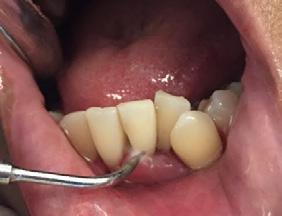

Paciente de 4 años y 8 meses, femenino que se presentó acompañada de su madre para valoración y consulta, presentando dentición mixta y movilidad clase 3 en el diente 71 y caries en diente 72, normoclusión molar y mordida cruzada anterior (Figura 1). Se realizó el plan de tratamiento integral, señalando la necesidad de llevar a cabo la exodoncia y la restauración. Dada la característica clínica presentada, se le conminó a la madre a atender ortodóncicamente a

Dentista y Paciente 24 Investigación clínica

Figura 1. Figura I. Exodoncia del 71 y caries proximal en diente 72.